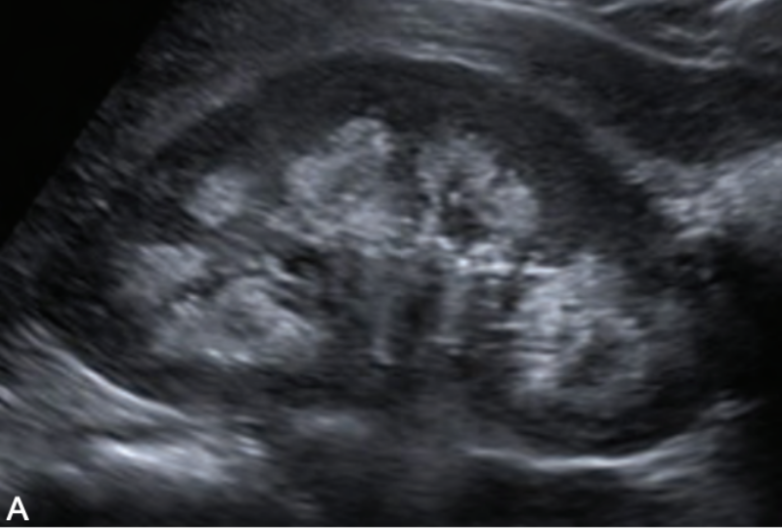

multicystic dysplastic kidney (MCDK)

MC form of cystic disease in neonates

unilateral non-functioning kidney

bilateral MCDK is incompatible with life

s/s: hematuria; infection; flank pain

increased risk of malignancy of kidney is not removed

SONO (neonates/children vs. adults): multicystic dysplastic kidney (MCDK)

neonates/children:

kidneys are multicystic and enlarged

renal artery atresia

adults:

atrophic kidneys

calcified

echogenic